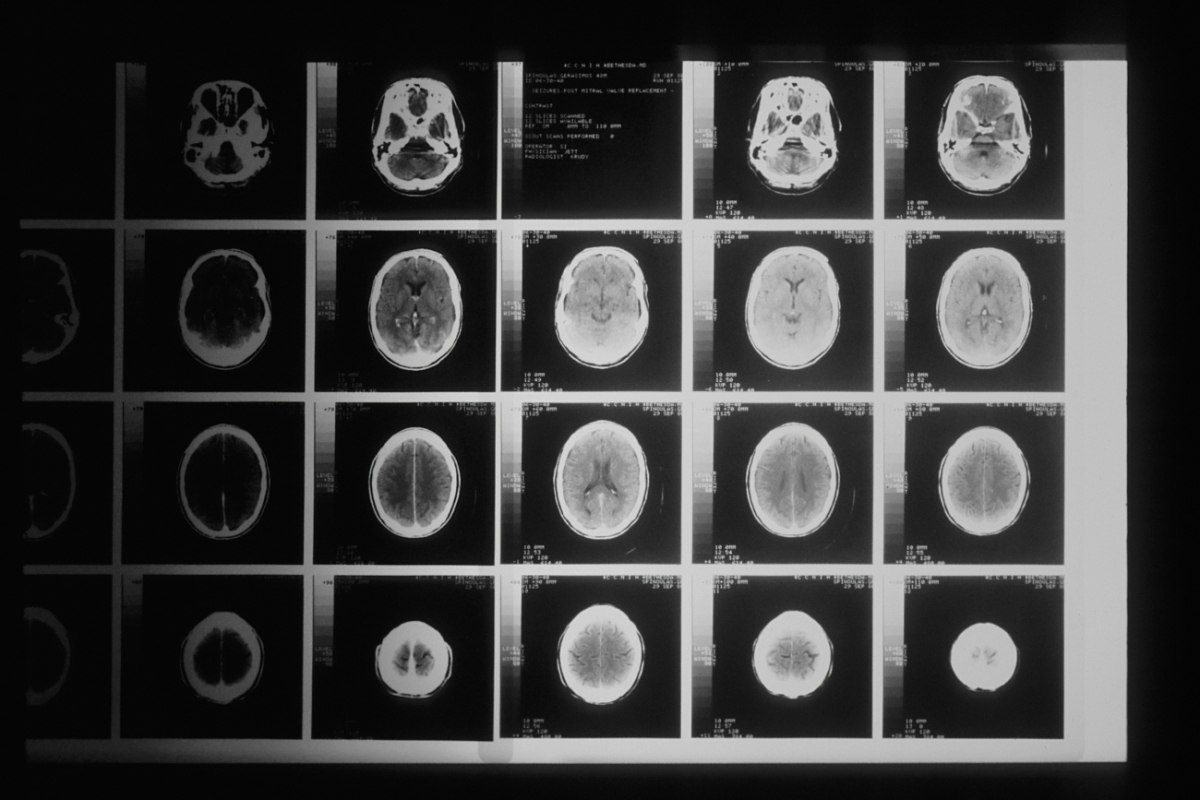

Περίπου 4.000 άτομα ηλικίας έως 90 ετών υποβλήθηκαν σε μαγνητικές τομογραφίες με σκοπό αποκαλυφθούν οι συνδέσεις μεταξύ των εγκεφαλικών τους κυττάρων.